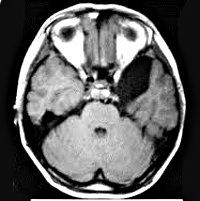

Введение контрастной среды в кисту во время ее пункции с последующей МРТ головного мозга выполняется для точного определения положения кисты и оценки ее размера. Эти данные необходимы нейрохирургу для планирования операции. Результаты контрастирования и анализа содержимого кисты позволяют уточнить показания к ее хирургическому лечению и выбрать наиболее приемлемый метод ее удаления. Процедура вмешательства похожа на укус абсцесса и подробно описана здесь. Подготовка пациента, облегчение боли, противопоказания и осложнения подробно описаны здесь.